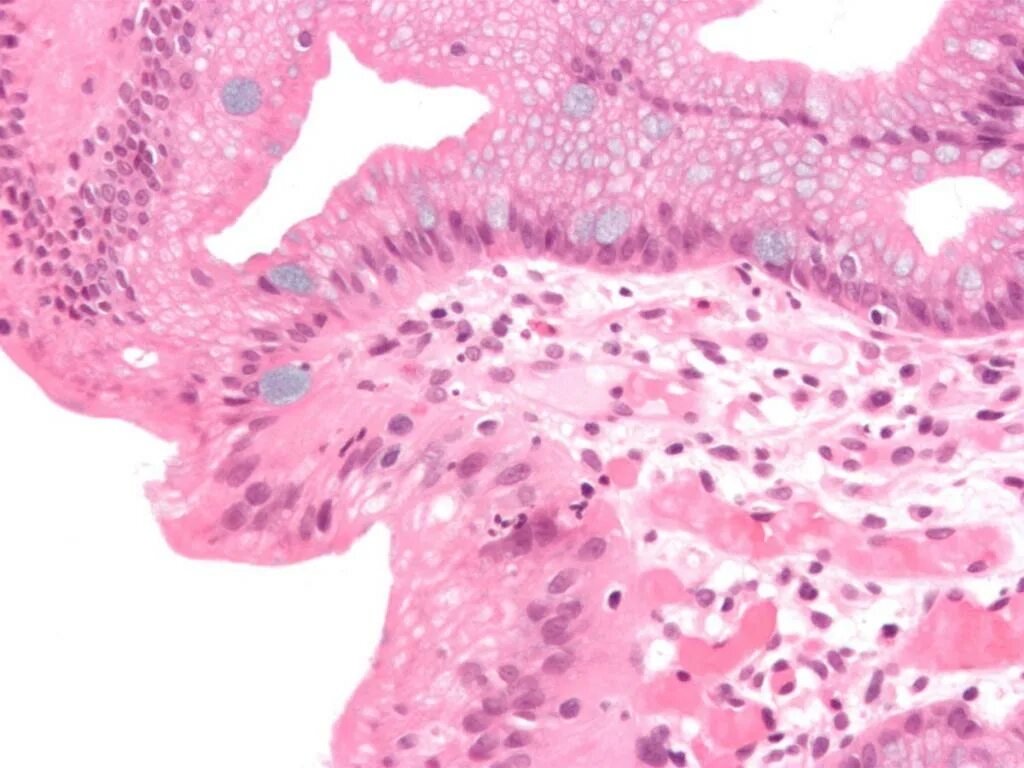

Реактивные изменения клеток метаплазированного эпителия